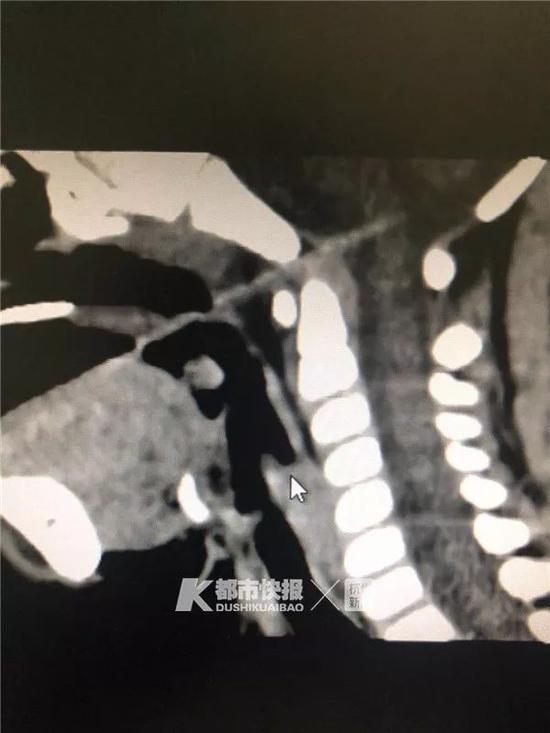

做完CT,省儿保的医生也吓了一跳:竹签从口腔,通过头颅和颈椎交界处,直接插进了脑子里,还伤到了脑干。核磁共振确诊,情况更加不妙,竹签插穿了整个脑干,随时有生命危险。

露在口腔外面的,只有3cm,在颅腔内戳进去的,也有3cm。